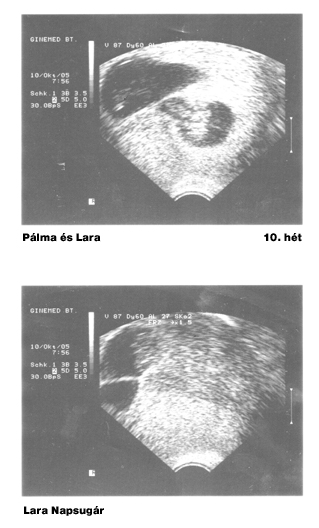

És íme a legelső UH-fotók:

Kép

úgy érzem, most végre elárulta magát: egyrészt 9-10 hetesen még LEHETETLEN megállapítani a magzat/ok (?) nemét, sőt még talán azt sem, hogy egy v. kétpetéjűek-e :shock:

másrészt, ha jól megnézitek a csatolt UH képeket, azokon 2005. okt. 10. dátum szerepel :roll:

bár igazából önmagát csapja be, ha notórius hazudozó, mindenesetre én jót derültem "Pálma Tűzvirág" és "Lara Napsugár"

sztárfotóin :)

nem tudom, járt-e valamelyikőtők a Péterfyben UH-n, de érdekelne , hogy közkórházban az UH készülék vajon miért azt nyomtatja a leletre fejlécként, hogy "Ginemed BT." ??

Azt pedig hogy kétpetéjűek már akár a 7. héten is lehet látni egy sima 3D-s UH-al is!!! Kedves szakember...

Nekünk 2004-ben a 7. héten mondták meg hogy kétpetéjű ikrek, most 2007-ben pedig a 10. héten. :D :D